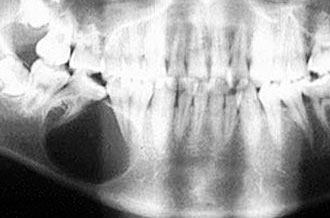

Киста челюсти (рентгенограмма)

Мало, или совсем себя не проявляя, киста видна, лишь когда появляется выпячивание челюсти с истончением его наружных плотных костных пластинок, на что обращает внимание сам больной или его окружающие. Часто при рентгенографии челюстей по тому или иному поводу киста обнаруживается как случайная находка. Рост ее иногда влечет столь значительные разрушения кости челюсти, что приводит к ее самопроизвольному перелому. Кроме того, проникновение в полость кисты гноеродных микробов может вызвать тяжелый воспалительный процесс с вовлечением в него костного мозга челюсти и развитием остеомиелита. Возможно перерождение корневой кисты как длительно текущего процесса в раковую опухоль.